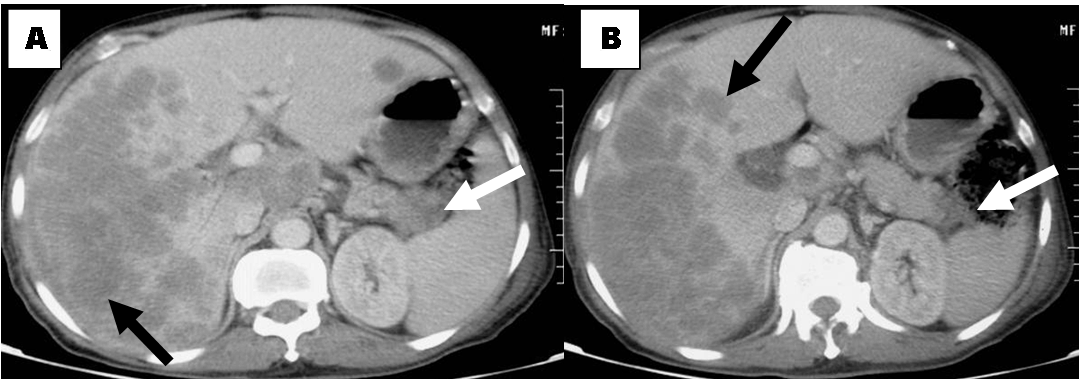

The patient had undergone abdominal contrast enhanced computed tomography (CT) scan which revealed a heterogeneous mass lesion of 3.2x3.3 cm size in the tail of pancreas with normal main pancreatic duct (MPD) diameter along with multiple well defined hypodense lesions of varying sizes in both lobes of liver with few of the lesions showing mild capsular bulge likely liver metastasis. Rest of the pancreas is normal in bulk and attenuation. Multiple enlarged and necrotic lymph nodes in periportal, peripancreatic, portocaval and aortocaval region; lytic lesions in dorsal (D9) vertebrae and mild ascites was also noted suggestive of metastatic disease. However, no evidence of vascular entrapment and adrenal gland metastasis was noted on imaging (Figure 1). In view of metastatic tumor on imaging, the patient underwent an ultrasound guided fine needle aspiration from the hypodense lesions of liver which showed features of metastatic adenocarcinoma (Figure 2). His carbohydrate antigen 19.9 (CA-19.9) level was found to be highly elevated (> 10000 IU/ml) confirming our diagnosis of unresectable metastatic pancreatic adenocarcinoma. Patient’s relatives took discharge from our centre in view of poor prognosis of the patient. However, he expired at home seven days after taking discharge from the hospital. Autopsy was not carried out in the patient.

Figure 1: Computed tomography scan of abdomen showing pancreatic tail mass (white arrow) with hepatic metastasis (black arrow showing hypodense lesions).